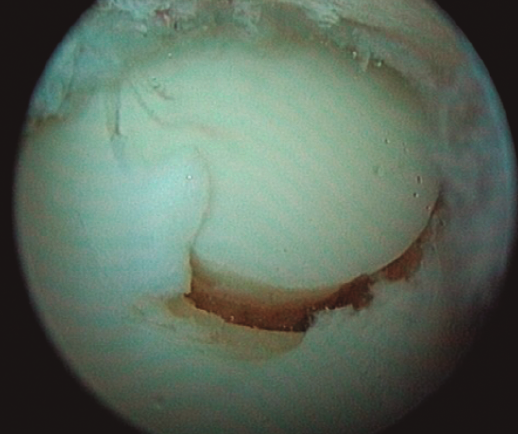

Figura 5. Lesión osteocondral de grado IIB en vertiente talar medial.

- Extracción de un cilindro osteocondral de la zona receptora de una profundidad de 15 mm y grosor dependiendo del tamaño de la lesión. Existen impactadores para compactar el hueso esponjoso subcondral (Figura 5).